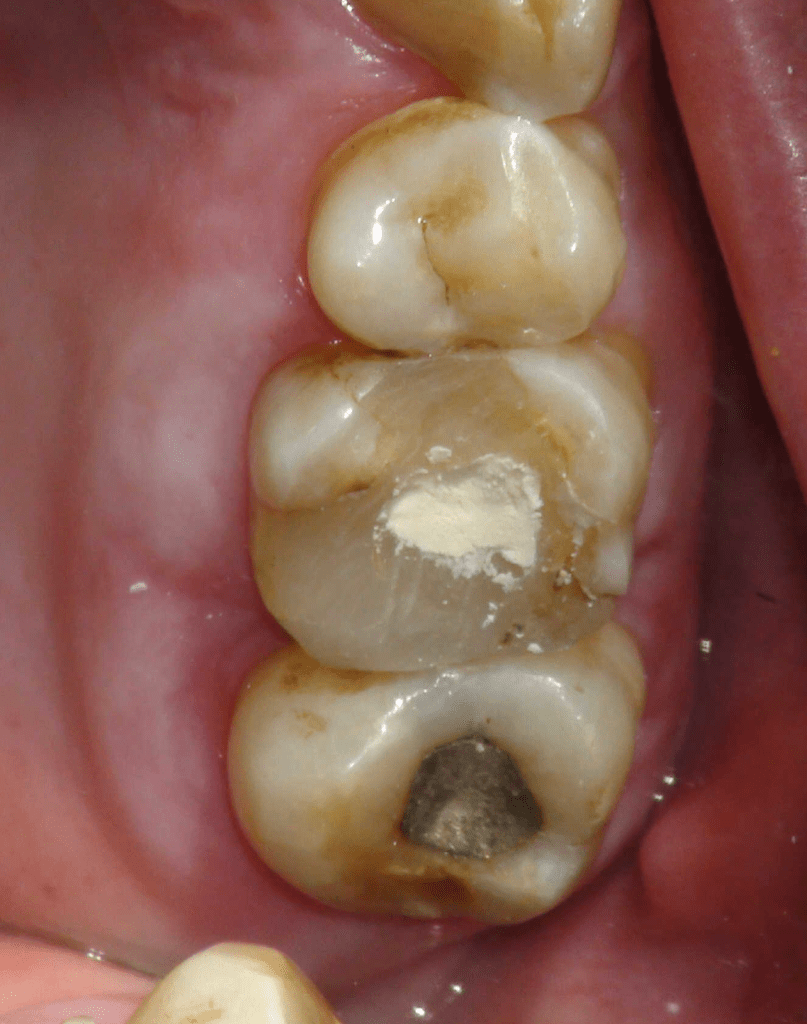

Reco preendo + 4 conductos molar superior